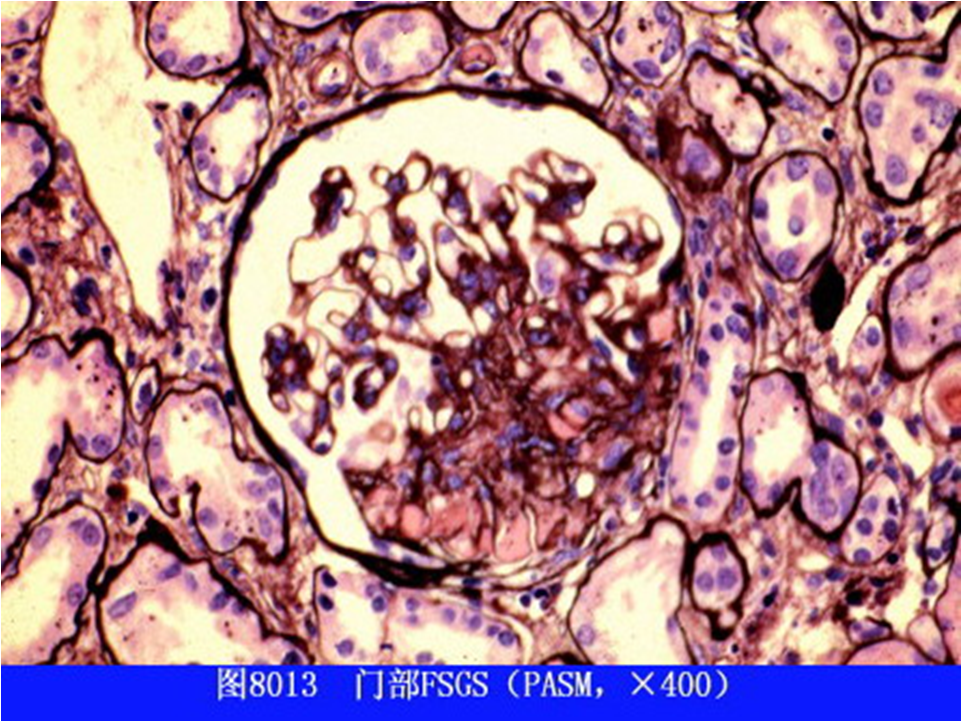

(五)局灶性节段性肾小球硬化

光镜下可见病变呈局灶、节段分布,表现为受累节段的硬化(系膜基质增多、毛细血管闭塞、球囊粘连等),相应的肾小管萎缩、肾间质纤维化。免疫病理检查显示IgM和C3在肾小球受累节段呈团块状沉积。电镜下可见肾小球上皮细胞足突广泛融合、足突与GBM分离及裸露的GBM节段。

根据硬化部位及细胞增殖的特点,FSGS可分为以下五种亚型:

①经典型:硬化部位主要位于血管极周围的毛细血管袢;

②塌陷型:外周毛细血管袢皱缩、塌陷,呈节段或球性分布,显著的足细胞增生肥大和空泡变性;

③顶端型:硬化部位主要位于尿极;

④细胞型:局灶性系膜细胞和内皮细胞增生同时可有足细胞增生、肥大和空泡变性;

⑤非特殊型:无法归属上述亚型,硬化可发生于任何部位,常有系膜细胞及基质增生。其中非特殊型最为常见,约占半数以上。

该病理类型约占我国原发性NS的5%~10%。本病好发于青少年男性,多为隐匿起病,部分病例可由微小病变型肾病转变而来。大量蛋白尿及NS为其主要临床特点(发生率可达50%~75%),约3/4患者伴有血尿,部分可见肉眼血尿。本病确诊时患者约半数有高血压和约30%有肾功能减退。 多数顶端型FSGS糖皮质激素治疗有效,预后良好。塌陷型治疗反应差,进展快,多于两年内进入终末期肾衰。其余各型的预后介于两者之间。过去认为FSGS对糖皮质激素治疗效果很差,近年的研究表明50%患者治疗有效,只是起效较慢,平均缓解期为4个月。NS能否缓解与预后密切相关,缓解者预后好,不缓解者6~10年超过半数患者进入终末期肾衰。